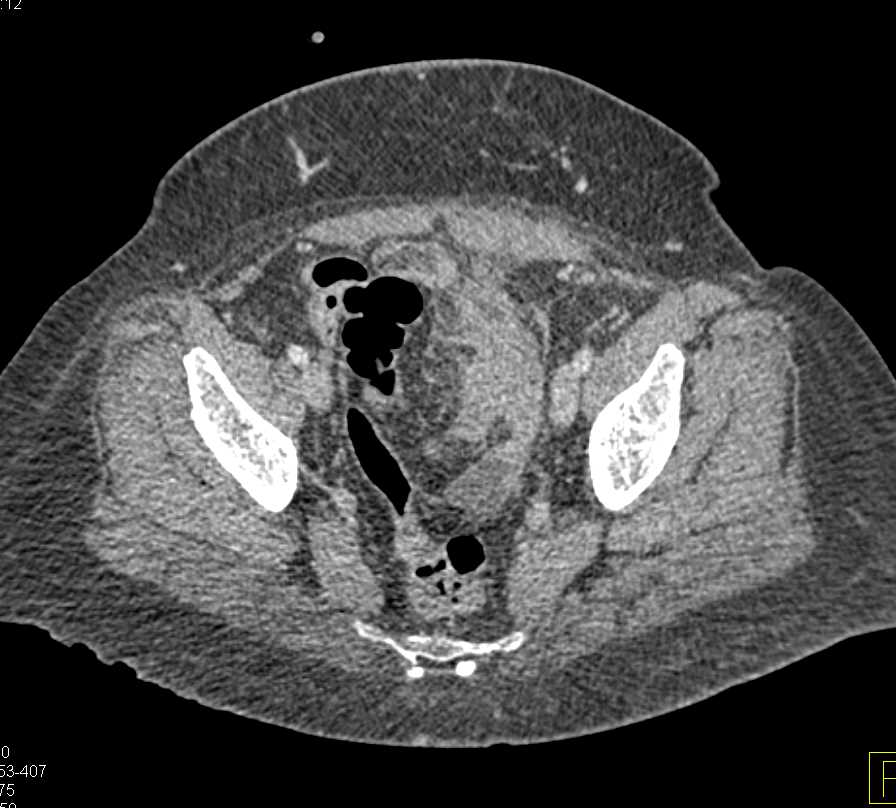

Diverticulitis with Abscess